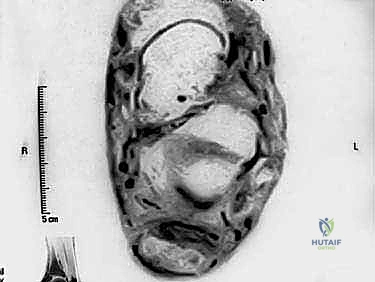

- التصوير بالرنين المغناطيسي (MRI): هو المعيار الذهبي والأداة الأقوى. يوفر صوراً ثلاثية الأبعاد وعالية الدقة تُظهر بدقة حجم التلف داخل الوتر، الأنسجة الندبية، حالة الجراب الزلالي، ومدى صلاحية وتر (FHL) لاستخدامه في الجراحة.

3. وتر العضلة الطويلة المثنية لإبهام القدم (FHL Tendon)

هنا يكمن السر الجراحي. العضلة الطويلة المثنية لإبهام القدم (Flexor Hallucis Longus) هي عضلة قوية تقع في عمق الساق الخلفية. يمر وترها خلف الكاحل وتحت القدم ليصل إلى إبهام القدم، ووظيفته الأساسية هي ثني الإصبع الكبير. يتميز هذا الوتر بأنه قوي جداً، طويل، وله مسار تشريحي يجعله قريباً جداً من وتر أخيل. الأهم من ذلك، أن عضلة (FHL) تنقبض في نفس المرحلة من دورة المشي التي تنقبض فيها عضلات الساق المرتبطة بوتر أخيل. لذلك، يعتبر هذا الوتر "المرشح المثالي" والمطابق حيوياً لتعويض وتر أخيل التالف.

الخطوة الرابعة: حصاد وتر (FHL)

يتم تحديد مسار وتر العضلة الطويلة المثنية لإبهام القدم. يقوم الجراح بتحرير الوتر من ارتباطاته السفلية في منتصف القدم، ويسحبه إلى منطقة الكعب. يتم التأكد من الحصول على طول كافٍ من الوتر لعملية النقل.